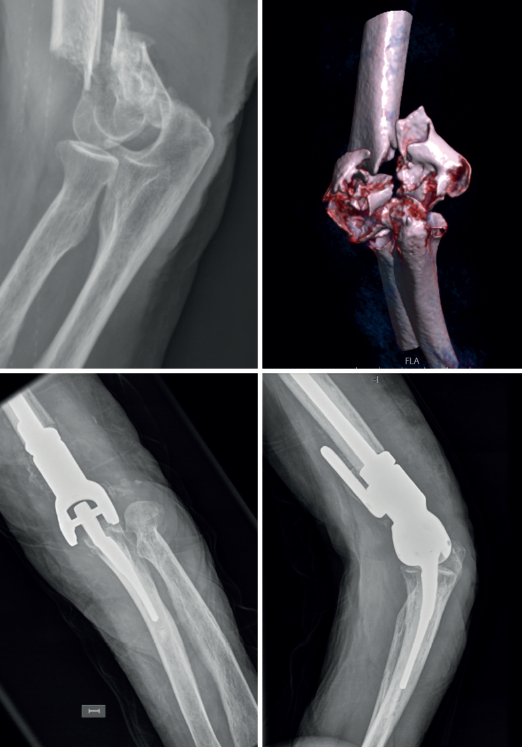

En consonancia con lo anterior, nosotros creemos que en la selección de la fractura que se va a intervenir con PTCodo es importante el uso de la tomografía computarizada para valorar y clasificar el tipo de fractura que tratar, porque si nos quedásemos con un estudio de radiología convencional difícilmente podríamos clasificar la fractura en el sistema AO (Figura 3). Todos los estudios incluidos para el tratamiento de fracturas de húmero distal mayoritariamente son fracturas de tipo C, pero en algunos casos A y B, por lo que nosotros adoptamos un protocolo propuesto por la Clínica Mayo para dicho tratamiento (Figura 2)(67), siendo muchas veces la decisión de emplear una PTCodo como tratamiento intraoperatoria. Mayoritariamente son fracturas cerradas, pero la existencia de fracturas abiertas no es una contraindicación, incluso se comunican fracturas de tipo IIIB de Gustilo(68).

Figura 3. Tratamiento de una fractura de tipo 13C3 de AO con prótesis total de codo, en una mujer de 62 años con una osteoporosis avanzada.